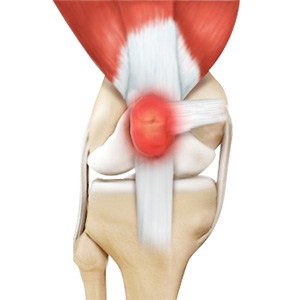

Quadriceps Tendon Rupture

The quadriceps tendon is a thick tissue located at the top of the kneecap. It works together with the quadriceps muscles to allow us to straighten our leg. The quadriceps muscles are the muscles located in front of the thigh.